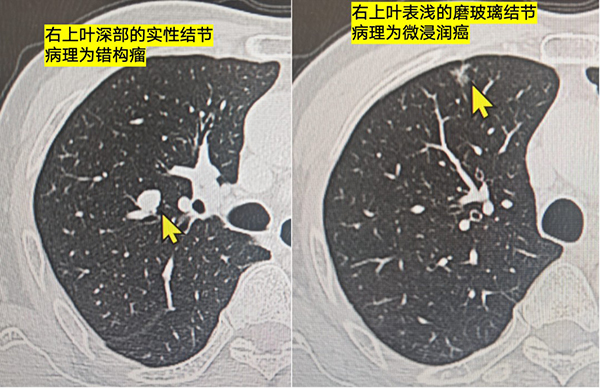

男性,50+岁,右肺上叶磨玻璃结节+右上叶实性结节

磨玻璃结节很典型,像早期肺癌

实性结节边界清晰,内部有脂肪密度,像错构瘤

病理显示,磨玻璃结节为微浸润癌,实性结节为错构瘤。